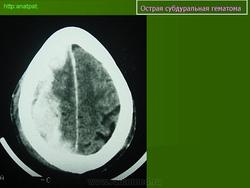

Субдуральные гематомы представляют собой кровоизлияние между твердой мозговой оболочкой и паутинной оболочкой, непосредственно покрывающей мозг, и обычно происходят вследствие разрыва сосуда на поверхности мозга. В большинстве случаев Субдуральные гематомы располагаются на обширной территории над лобными и теменными долями. Острые субдуральные гематомы - это кровоизлияния, произошедшие в сроки до 72 часов и выглядящие на КТ головного мозга как гиперденсивные образования. Подострые субдуральные гематомы это кровоизлияния от 3 до 20 дней, которые на КТ выглядят как изоденсные или гиподенсные относительно головного мозга образования. Хронические Субдуральные гематомы - это гематомы старше 21 дня (3 недель), которые выглядят, как гиподенсные образования на КТ. Тем не менее, Субдуральные гематомы могут быть смешанными, например, когда происходит острое кровоизлияние в полость хронической гематомы. Острые субдуральные гематомы встречаются у 5-25% пациентов с тяжелой черепно-мозговой травмой. Хронические субдуральные гематомы насчитывают 1-5.3 на 100 000 населения в год. Более свежие исследования демонстрируют более высокую частоту гематом в связи с улучшением техники нейровизуализации. В противоположность эпидуральным гематомам, которые обычно не распространяются за пределы костных швов черепа, субдуральные гематомы могут быть очень протяженными по площади, распространяясь от серпа мозга до намета мозжечка. Острые субдуральные гематомы вследствие травмы наиболее опасные из всех повреждений мозга, сопровождающиеся наибольшей летальностью, если вовремя не провести хирургическое вмешательство.

Острая субдуральная гематома.

Острые субдуральные гематомы - это кровоизлияния, произошедшие в сроки до 72 часов и выглядящие на КТ головного мозга как гиперденсивные образования. Подострые субдуральные гематомы это кровоизлияния от 3 до 20 дней, которые на КТ выглядят как изоденсные или гиподенсные относительно головного мозга образования. Хронические Субдуральные гематомы - это гематомы старше 21 дня (3 недель), которые выглядят, как гиподенсные образования на КТ. Тем не менее, Субдуральные гематомы могут быть смешанными, например, когда происходит острое кровоизлияние в полость хронической гематомы. Острые субдуральные гематомы встречаются у 5-25% пациентов с тяжелой черепно-мозговой травмой. Хронические субдуральные гематомы насчитывают 1-5.3 на 100 000 населения в год. Более свежие исследования демонстрируют более высокую частоту гематом в связи с улучшением техники нейровизуализации.

В противоположность эпидуральным гематомам, которые обычно не распространяются за пределы костных швов черепа, субдуральные гематомы могут быть очень протяженными по площади, распространяясь от серпа мозга до намета мозжечка. Острые субдуральные гематомы вследствие травмы наиболее опасные из всех повреждений мозга, сопровождающиеся наибольшей летальностью, если вовремя не провести хирургическое вмешательство.